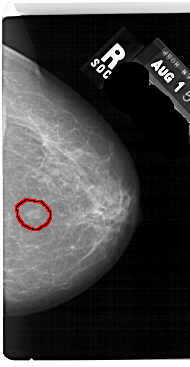

A_1563_1.RIGHT_MLO

RIGHT_CC LINES 5491 PIXELS_PER_LINE 2836 BITS_PER_PIXEL 12 RESOLUTION 43.5 OVERLAY

FILE: A_1563_1.RIGHT_CC.OVERLAY

TOTAL_ABNORMALITIES 1

ABNORMALITY 1

LESION_TYPE MASS SHAPE OVAL MARGINS ILL_DEFINED

ASSESSMENT 4

SUBTLETY 4

PATHOLOGY BENIGN

TOTAL_OUTLINES 1

BOUNDARY